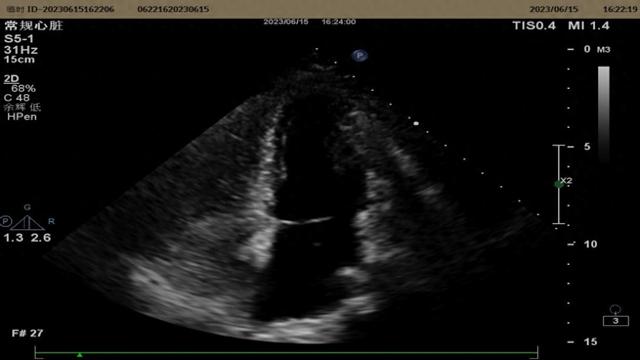

刘小姐头痛数年 , 多次检查未见异常 。 最后在医生的建议下进行右心声学造影检查发现左心内大量微气泡 , 判断引起头痛的原因可能是卵圆孔未闭 , 行介入封堵术后头痛消失 。

右心声学造影阴性 右心声学造影阳性

右心声学造影是在超声心动图成像时 , 经外周静脉注入声学造影剂 , 使右心系统增强显影的技术 。 目前常用造影剂为“生理盐水+空气+自身血液(8ml:1ml:1ml)” 。